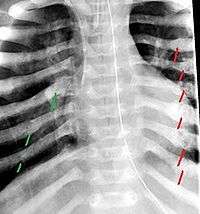

The material factual allegations of the amended complaint are as follows. Plaintiff was born on May 14, 1970. On repeated occasions during the first year of her life she was severely beaten by her mother and the latter’s common law husband, one Reyes. On April 26, 1971, when the plaintiff was eleven months old, her mother took her to the San Jose Hospital for examination, diagnosis, and treatment. The attending physician was defendant Dr. Flood, acting on his own behalf and as agent of the defendant San Jose Hospital. At the time, the plaintiff was suffering from a comminuted spiral fracture of the right tibia and fibula, which gave the appearance of having been caused by a twisting force. Plaintiff’s mother had no explanation for this injury. Plaintiff had bruises over her entire body. In addition, she had a non-depressed linear skull fracture which was then in the process of healing. Plaintiff demonstrated fear and apprehension when approached. Inasmuch as all plaintiff's injuries gave the appearance of having been intentionally inflicted by other persons, she exhibited the medical condition known as the battered child syndrome.

It is alleged that proper diagnosis of plaintiff's condition would have included taking X-rays of her entire skeletal structure, and that such procedure would have revealed the fracture of her skull. Defendants negligently failed to take such X-rays, and thereby negligently failed to diagnose her true condition. It is further alleged that proper medical treatment of plaintiff's battered child syndrome would have included reporting her injuries to local law enforcement authorities or juvenile probation department. Such a report would have resulted in an investigation by the concerned agencies, followed by a placement of plaintiff in protective custody until her safety was assured. Defendants negligently failed to make such report.

The complaint avers that as a proximate result of the foregoing negligence plaintiff was released from the San Jose Hospital without proper diagnosis and treatment of her battered child syndrome, and was returned to the custody of her mother and Reyes who resumed physically abusing her until she sustained traumatic blows to her right eye and back, puncture wounds over her left lower leg and across her back, severe bites on her face, and second and third degree burns on her left hand.

On July 1, 1971, plaintiff was again brought in for medical care, but to a different doctor and hospital. Her battered child syndrome was immediately diagnosed and reported to local police and juvenile probation authorities, and she was taken into protective custody. Following hospitalization and surgery she was placed with foster parents, and the latter subsequently undertook proceedings to adopt her. Plaintiff's mother and Reyes fled the state, but were apprehended, returned for trial, and convicted of the crime of child abuse.[1]